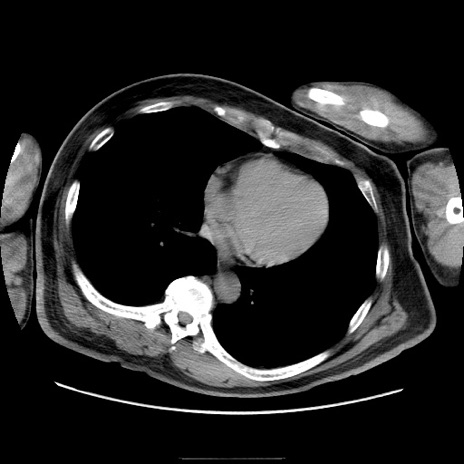

症例22(横断像)

【症例】50歳代男性

【主訴】腹痛

【現病歴】AVMからの被殻出血のため回復期リハ病棟入院中。 本日午後3時頃急に下腹部痛が出現した。

【既往歴】AVM、被殻出血、虫垂炎、高血圧

【身体所見】意識晴明、左半身不全麻痺、会話の理解は良好、36.5°C、腹部:膨隆、全体に板状硬、下腹部正中に圧痛点あり、反跳痛-、筋性防御不明、右下腹部にope scar

【データ】WBC 9400、CRP 0.06